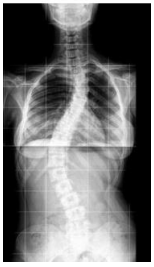

M., 23 anos, apresentou o raio-X abaixo para o seu médico:

É CORRETO afirmar que ele tem: